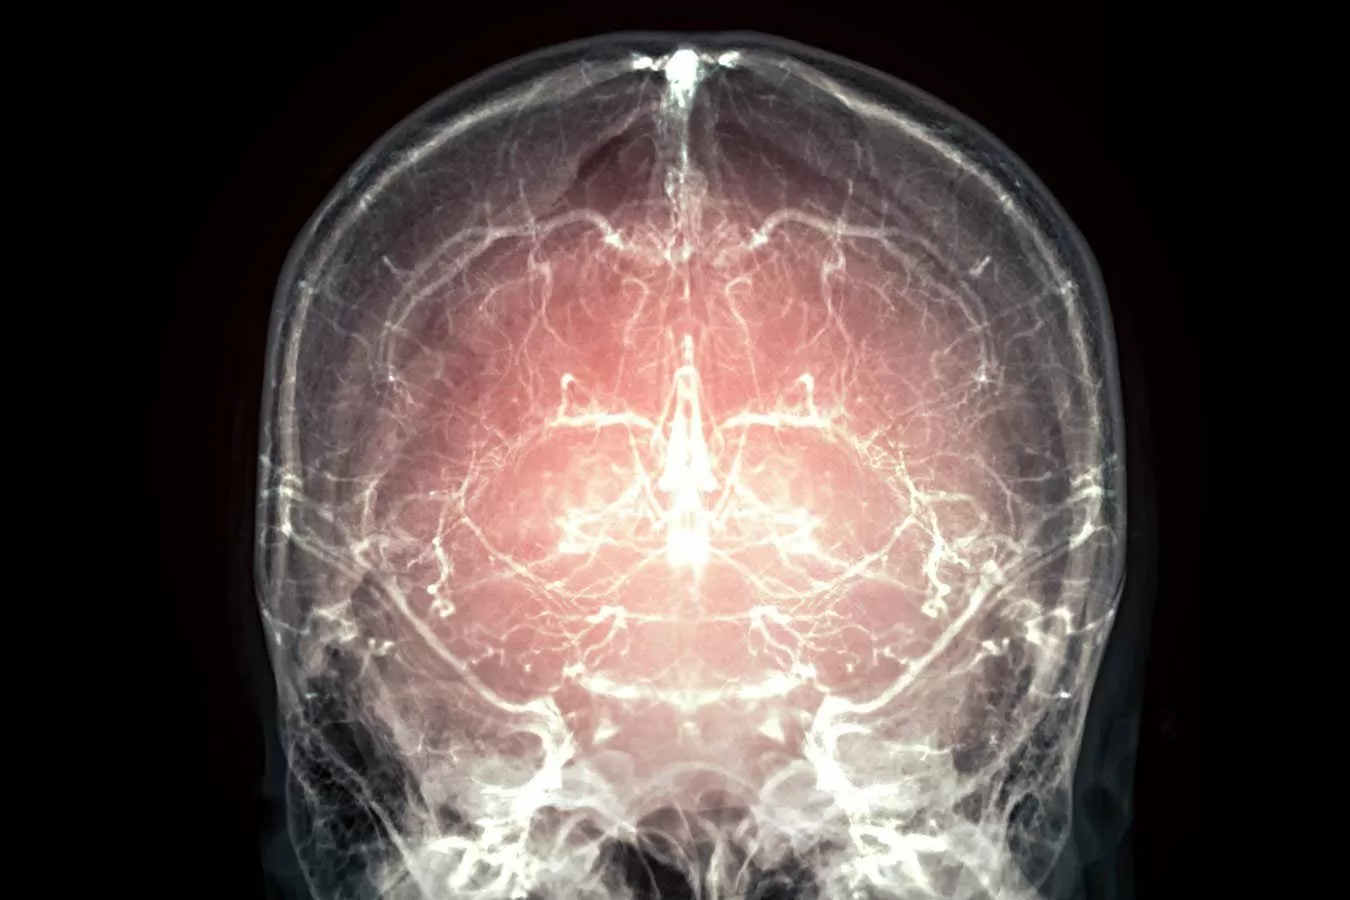

The concept of cryonics, or preserving the body or brain at extremely low temperatures in the hopes of future revival, has been a topic of much debate and controversy. However, recent advancements in technology have brought forth a new possibility – the cryopreservation of brains with minimal damage and preserved cellular activity. This breakthrough has led to the question of whether this could also be applied to those with terminal illnesses, allowing them to potentially continue their lives in the future. One such case that has sparked much interest is the cryopreservation of a pig’s brain, which has raised the possibility of preserving human brains for future revival.

The experiment, conducted by a team of scientists at 21st Century Medicine, involved cooling a pig’s brain to -135 degrees Celsius. This temperature is low enough to halt all biological activity, preserving the brain in a state of suspended animation. The brain was then thawed and examined under a microscope, revealing that the cellular structure and connections remained intact, with minimal damage. This groundbreaking achievement has given hope for the future of cryopreservation and its potential applications.